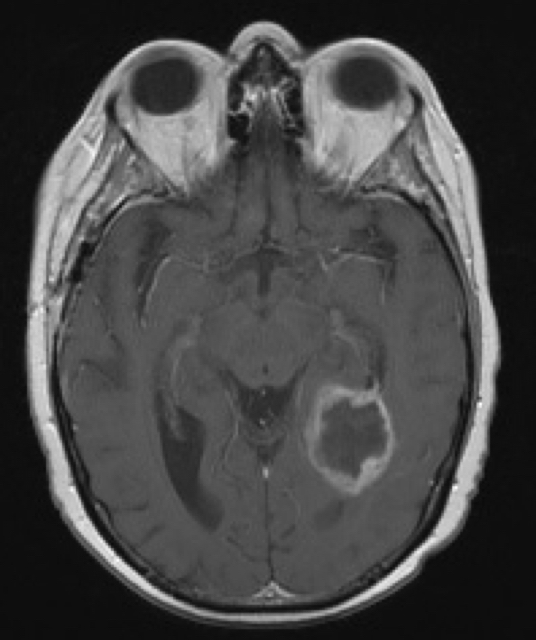

Diagnostic tests. Sagittal T1-weighted magnetic resonance imaging (MRI) revealed a 3.7 × 3.0 × 3.3 cm, irregular, inhomogeneous mass in the posterior right frontal lobe with extensive surrounding vasogenic edema. Another mass in the left posteromedial temporal lobe straddling the left ventricular trigone was also identified, measuring 2.7 × 2.2 × 2.6 cm (Figure 1). The masses demonstrated irregular, thickened peripheral enhancement with a necrotic/cystic internal component and increased peripheral cerebral blood flow on the perfusion images.